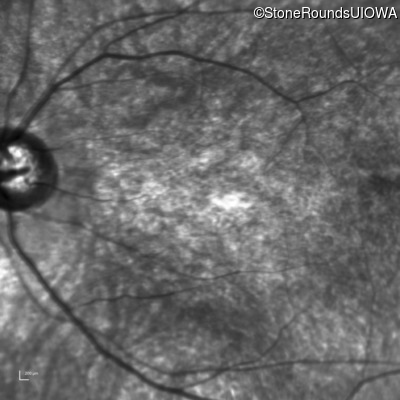

Age at visit: 6 years

OD OS

This 6 year old male first experienced a loss of visual acuity at age 5. His acuity was previously normal. He is otherwise healthy.